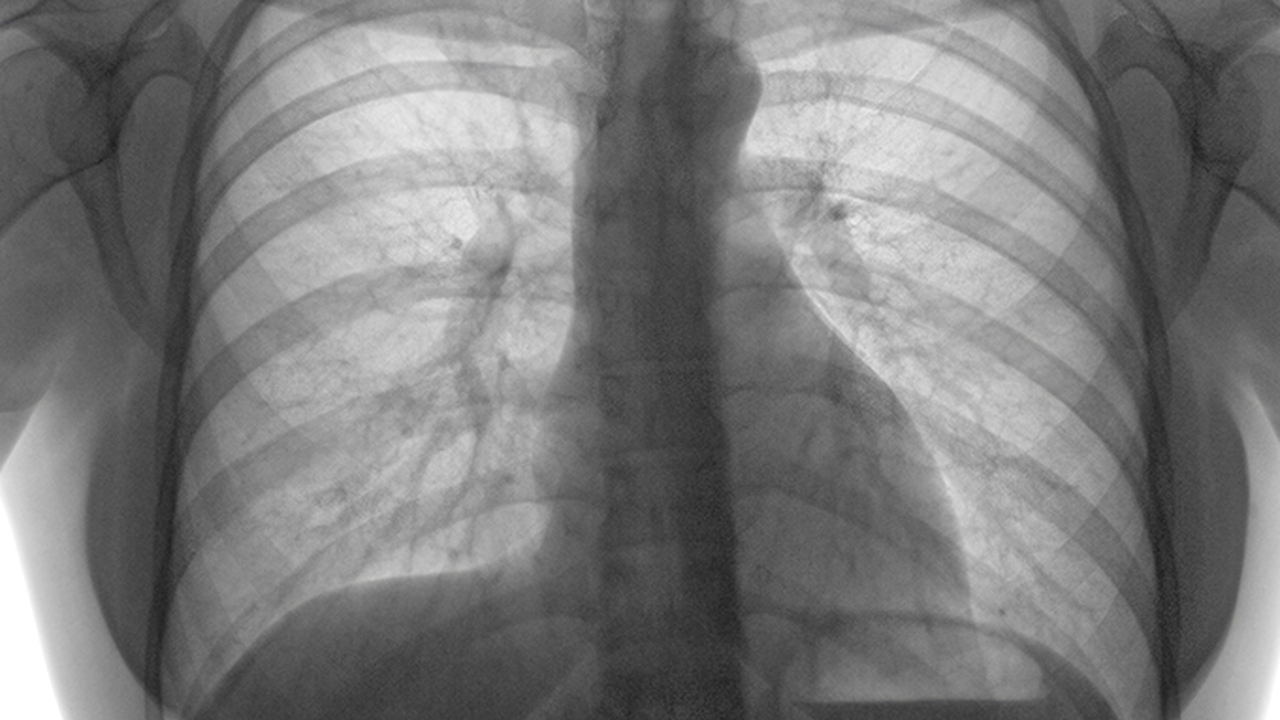

肺癌是一种常见的恶性肿瘤,其发病原因复杂,包括吸烟、环境污染、职业暴露、遗传因素等。早期诊断和规范治疗对提高患者生存率至关重要。目前,肺癌的治疗方法主要包括手术、放疗、化疗、靶向治疗和免疫治疗等,医生会根据患者的具体情况制定个体化的治疗方案。